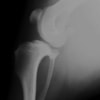

本症例は、走った後に左後肢を挙上していることを主訴に来院されました。触診時に左膝関節のクリック音を聴取、レントゲン検査にて左脛骨の前方変位が認められました。術中に、前十字靱帯の断裂及び内側半月板の損傷、内側の軟部組織の顕著な腫脹を確認。半月板切除、TPLOを実施しました。周囲組織への炎症の波及もあったため回復に時間を要しておりますが、徐々に跛行頻度は減少傾向にあり、現在も経過観察中です。術前に約29°あったTPAは術後に約10°まで矯正されました。

術前写真

手術前後のTPA(脛骨高平部の角度)を測定しています。

約29°から約10°へ矯正されています。